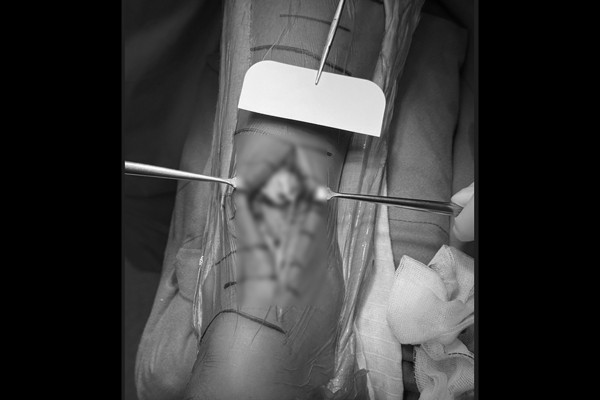

수술실에서 파열되어 완전히 끊어진 아킬레스건이 확인됩니다.